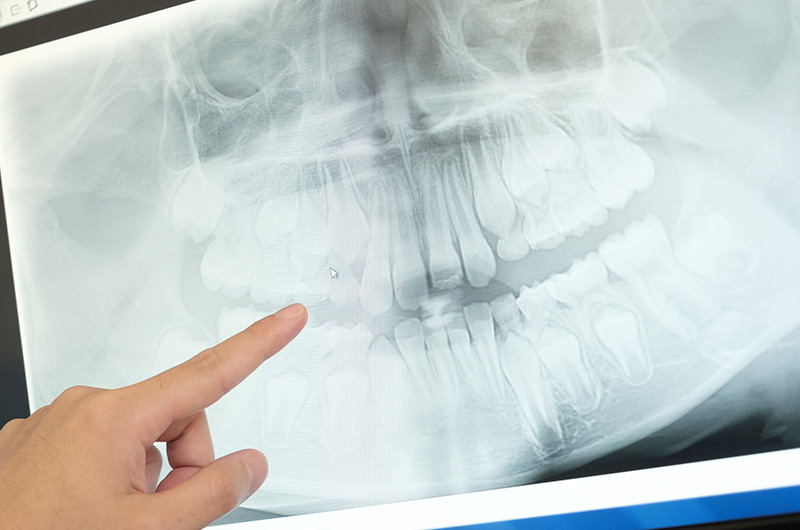

レントゲン検査

普段は気づけない病気を見逃さないために

定期検診へお越しになられている方へ、年に1回、レントゲン検査を行っております。(希望者)

成長経過のお子様の場合、生まれつき歯がない病気(先天性欠損)やその他先天性の疾患など、大人の方の場合、骨の中の病気など、普段の診察ではなかなか気づけない病気が見つかることがよくあります。

また、眼で確認できない部位のむし歯が発見されることもよくあります。レントゲン検査は早期発見・早期治療につながります。

こうした目で見ただけでは発見できない病気を見逃さないためにも、年に1回のレントゲン検査は大切です。